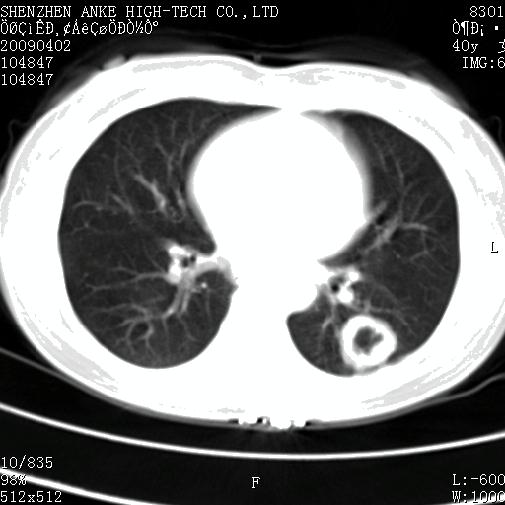

以下是引用随光逐影在2009-4-2 12:16:00的发言:[br]考虑左肺下叶背段继发性肺结核,结核球形成;建议追踪复查。

以下是引用gudu医生在2009-4-2 11:27:00的发言:[br]周围型肺癌

以下是引用卜一在2009-4-2 13:31:00的发言:[br][br] [br] 空洞壁厚不均 胸膜凹陷征。周围型肺癌可能 不排除干酪坏死型肺结核及坏死性肉芽肿。 [br] [br]支持!

以下是引用ct诊断高手在2009-4-2 13:04:00的发言:[br]空洞壁厚不均 胸膜凹陷征。周围型肺癌可能 不排除干酪坏死型肺结核及坏死性肉芽肿。